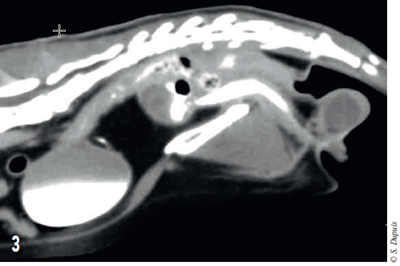

Une urétrographie de contraste positif est réalisée et montre que le produit de contraste injecté se répand dans les cavités de la masse (figure 3).

Photo 3 – Coupe sagittale tomodensitométrique de l’abdomen. Visualisation du produit de contraste injecté dans l’urètre